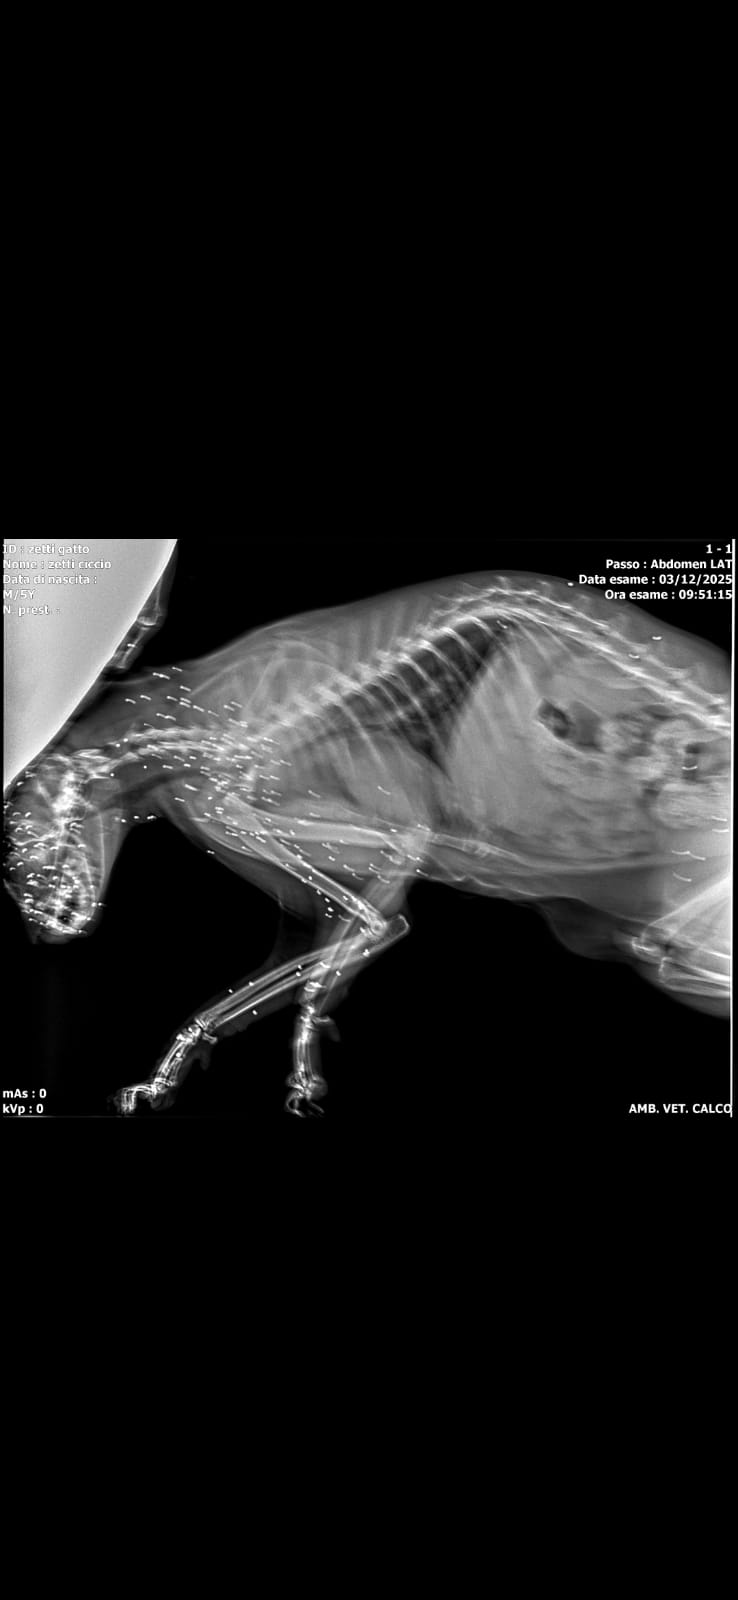

Portato con urgenza dal veterinario è emersa la terribile verità: il gatto è stato preso a fucilate e i pallini che lo hanno centrato oltre che penetrare in diverse parti del corpo lo hanno reso cieco per sempre.